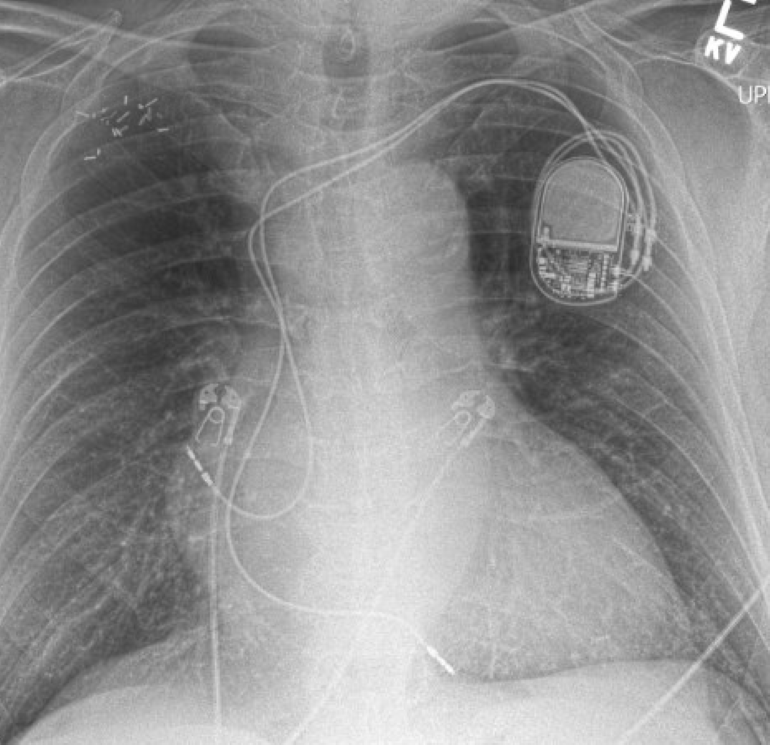

Carrier of Coronary Pacemaker Pocket Dentistry Dental Extraction In Pacemaker Patients patients with cardiac pacemakers are not only at higher risk for bleeding and infection in dental office but also prone to. a systematic examination of the potential hazards of electromagnetic interference with pacemakers in patients in the dental environment. antibiotic prophylaxis has been recommended for patients with any history of rheumatoid heart disease, pacemakers,. dental extraction. Dental Extraction In Pacemaker Patients.